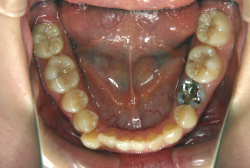

「左奥歯でものが噛めない」という主訴で来院したケースです。診断の結果、基本的には「叢生」という隙間が足りないと言うことが原因の凸凹症例でしたが、左下の乳歯が高校生になってもまだ残存している状態で、そのせいで噛み合わせが極端に悪くなっていました。

検査の結果、乳歯の下には後継ぎの永久歯が先天的に欠如していました。配列の凸凹が厳しく非抜歯で矯正することは難しく、仮に無理をして非抜歯治療をしても後々「後戻り」が懸念されることから、このような症例の場合は通常、上下顎左右第一小臼歯を抜歯させていただくのですが、左下は乳歯を抜歯して、第一小臼歯は残すことにしました。これで結果として、小臼歯部を上下左右で一つずつ減らしたのと同じ状況になります。治療後は歯並びが綺麗になっただけでなく、噛み合わせ的にも正しい状態が確立しています。

このように、先天的に永久歯が足りないという症例は最近増えています。親知らずはなくても特に問題になりませんが、その他の歯が足りないと言うのは審美的にも機能的にも重大な障害となります。しかし、矯正治療を正しく行えば、結果として歯がすべてあった場合と全く同じ仕上げにすることも可能です。